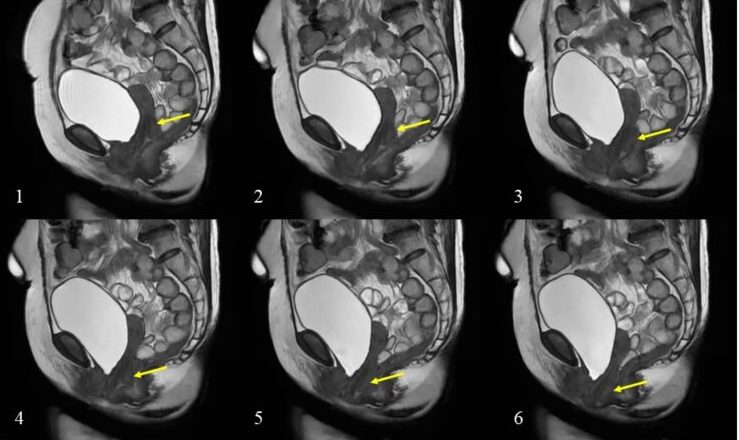

子宮脱予防で用いられるペッサリーリングのCT画像所見。